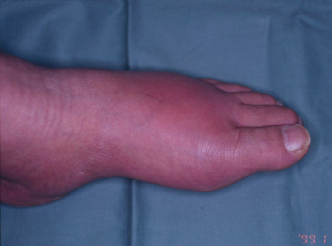

拇趾基関節の痛風発作

左拇趾基関節の急性関節炎により前足部全体に腫脹、発赤がみられる。

1: 谷口敦夫先生(東京女子医大膠原病リウマチ痛風センター)ご提供